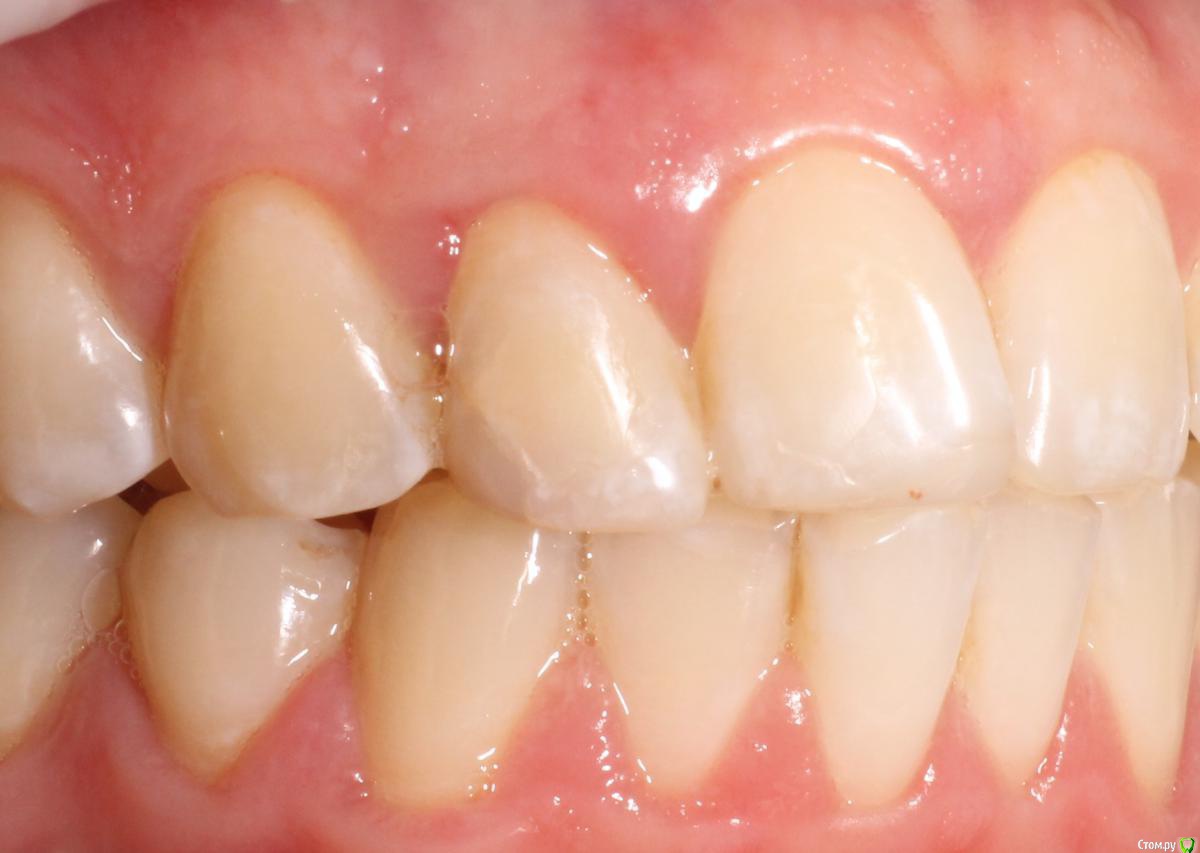

MenshikovDV Опубликовано 2 апреля, 2015 Поделиться Опубликовано 2 апреля, 2015 (изменено) Зуб 1.2 отлом коронковой части зуба, на период ожидания приема у хирурга и ортопеда (2 дня) приклеен к соседям. Вся процедура в одно посещение. Где-то часа два. Я ортопед, хирургия не моя, фото мои Изменено 2 апреля, 2015 пользователем MenshikovDV 19 Ссылка на комментарий

MenshikovDV Опубликовано 7 апреля, 2015 Автор Поделиться Опубликовано 7 апреля, 2015 Класс! Аккуратно сработали!Единственно, думаю что аугментации была бы желательна.Спасибо.Время покажет. Ссылка на комментарий